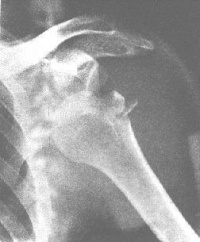

X线征象是构成肩关节的肩肿骨、肩盂和肱骨头的两关节面失去正常平行的关系。按肱骨头分离的程度和方向,分为以下几型:

1.肩关节半脱位:关节间隙上宽下窄。肱骨头下移,尚有一半的肱骨头对向肩盂。

2.肩关节前脱位:最多见。其中以喙突下脱位尤为常见。正位片可见肱骨头与

肩盂和肩胛颈重叠,位于喙突下0.5cm-1.0cm 处。肱骨头呈外旋位,肱骨干轻度外展。肱骨头锁骨下脱位和盂下脱位较少见。

3.肩关节后脱位:少见。值得注意的是正位片肱骨头与肩盂的对位关系尚好,关节间隙存在,极易漏诊。只有在侧位片或腋位片才能显示肱骨头向后脱出,位于肩盂后方。